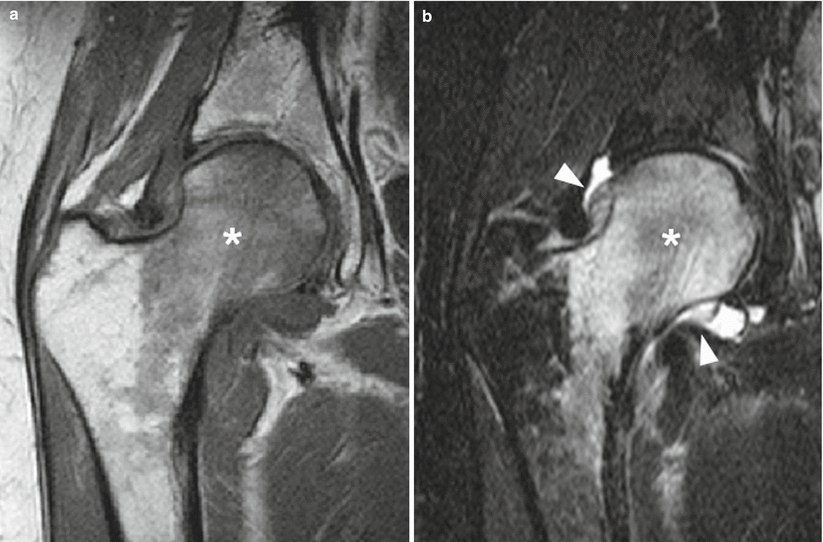

Bone Edema In Hip. Mr imaging is the modality of choice when clinical examination is suspect for hip disease and plain radiographs are normal or equivocal. Bone marrow edema affecting the hip is neither a specific mr imaging finding nor a specific diagnosis and may be encountered in a variety of hip disorders due to different etiologies.

Coronal mri of hips was acquired in. An mri scan of a hip affected by transient osteoporosis will usually reveal bone marrow edema. What is bone edema hip"for example, a patient may fracture a hip and, despite some pain, may not be severely disabled by the injury.

Bone marrow edema can happen with fractures and other serious bone or joint injuries. A core biopsy specimen of bone marrow edema syndrome (stain, hematoxylin and eosin; Traumatic bone marrow edema results in a small but measurable increase in ct attenuation values secondary to hemorrhage and increased interstitial fluid within the marrow cavity.